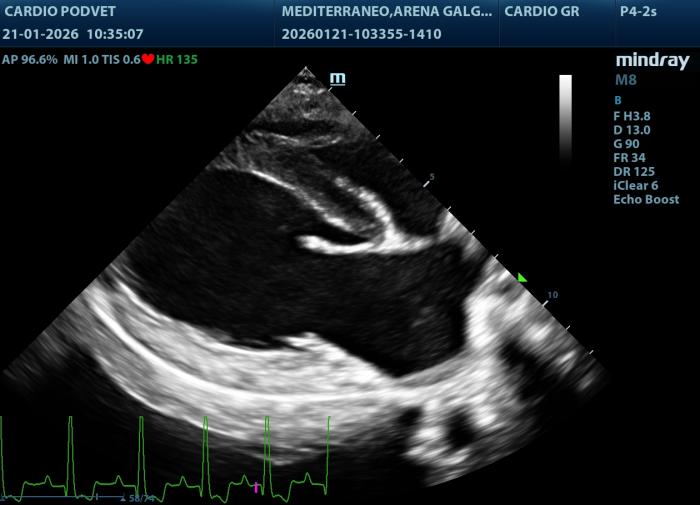

Posteriormente se obtiene este índice mediante la siguiente fórmula: LAI= AML (mm) + PML (mm)]/APL(mm). El área mitral se calcula obteniendo los diámetros de la válvula mitral (AM) en la vista paraesternal derecha transversal a la altura de la válvula mitral, con los diámetros anteroposterior (dAP) y diámetro transcversal (dT) (Figura2) y la fórmula: AM = (π x (dAP/2) x (dT/2))/100. Y por último los diámetros y áreas de las valvas mitrales medidas en la vista paraesternal derecha 4 cámaras durante la diástole (Figura3A-B).